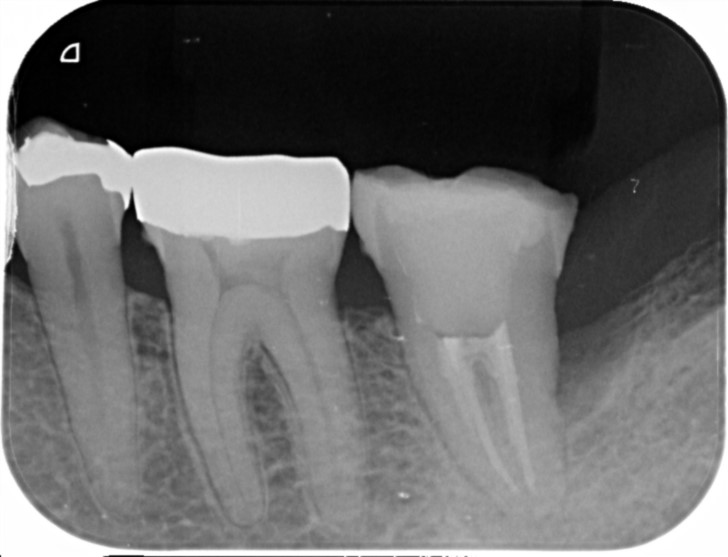

2023/8 他院での被せ物を外した状態

2023/8 根っこの治療が終わって仮歯が入っている状態

2024/1

2024/5 根っこの治療を再度行いしっかりお薬が入っています。

治療部位 | 左上5番 |

費用 | 約10万円 |

治療期間 | 5ケ月 |

4年ほど前に他院さんで治療した歯が痛むということで当院には精密根管治療を希望してお越しになられました。

根っこの治療が終わってもすぐに被せ物は被せず、仮歯で様子を見ました。